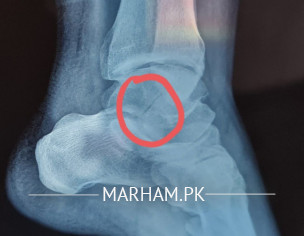

My husband fell down from stairs and had a fracture in his talus bone. The doctors are saying that we need to operate it and insert screws to fix the bone that has been cracked and dislocated. Can it be fixed without operation only with plaster. Xray has been attached kindly advise